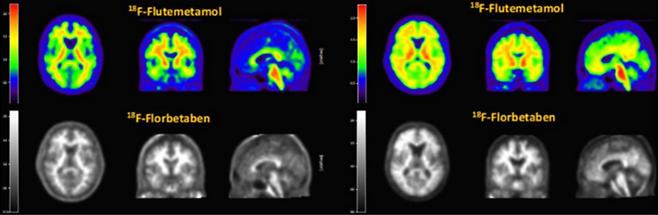

지난 2024년 12월 초 한국에자이의 알츠하이머 치매 치료제 레켐비(성분명 레카네맙)가 국내 출시되면서 지난 1년간 국내 시장은 듀켐바이오를 주목해왔다. 듀켐바이오가 레켐비 처방을 위한 선결요건인 PET-CT 진단제 뉴라체크와 비자밀을 국내 생산·유통하는 유일한 회사이기 때문이다.

국내 시장에 허가를 받은 다양한 알츠하이머 치매 진단방법이 있지만 레켐비 처방을 받으려면 PET-CT를 촬영하거나 뇌척수액 진단(CSF)을 통해 알츠하이머 치매를 확진받아야 한다. CSF는 뇌척수액을 추출해 진단하는 것인 만큼 PET-CT에 비해 통증이 있다. 그외 다른 진단방법은 고비용의 PET-CT 촬영 여부를 결정하기 전 보조수단으로 사용될 뿐이다.

듀켐바이오가 독점 공급계약을 따낸 GE헬스케어의 비자밀과 바이엘의 뉴라체크는 다양한 글로벌 치매 신약 임상시험에서 환자 선정 및 치료 효과 판단에 사용되고 있다. 이 두 제품의 진단용 동위원소인 F-18은 반감기가 110분으로 제조 후 2시간이면 약효가 절반으로 감소한다. 이 때문에 비자밀, 뉴라체크 공급을 위한 계약 과정에서 듀켐바이오가 가진 전국 의약품 제조·품질관리기준(GMP) 생산시설과 물류 시스템이 높은 점수를 받았다.

그는 “우리가 뉴라체크, 비자밀 두 가지 진단제를 제조하고 있는데 병원이 뉴라체크를 쓰다가 비자밀로 바꾸는 경우, 비자밀을 쓰다가 뉴라체크로 바꾸는 경우는 거의 없었다”며 “제품마다 이미지 차이가 작지만 분명히 존재하므로 갑자기 다른 진단제로 바꿀 경우 기존 환자의 이미지는 더 이상 환자 상태를 비교하는 용도로 쓸 수 없게 되기 때문”이라고 말했다.